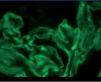

The anatomical pathology described a total of 49 glomeruli, three of them sclerosed and the structure of the others was extensively affected. Fibrinoid necrosis and extracapillary cell and circumferential proliferation were found in 100% of the glomeruli. The small vessels also had necrotising vasculitis. The direct IF study provided a linear and diffuse positive in the glomerular basement membrane, with IgG positive and the rest of the antibodies negative. In summary, extracapillary glomerulonephritis was detected with intense involvement of 100% of the glomeruli of the sample and IF typical of anti-GBM Ab-mediated extracapillary glomerulonephritis (type I), see Figures 1 and 2.

Figure 2. Immunofluorescence